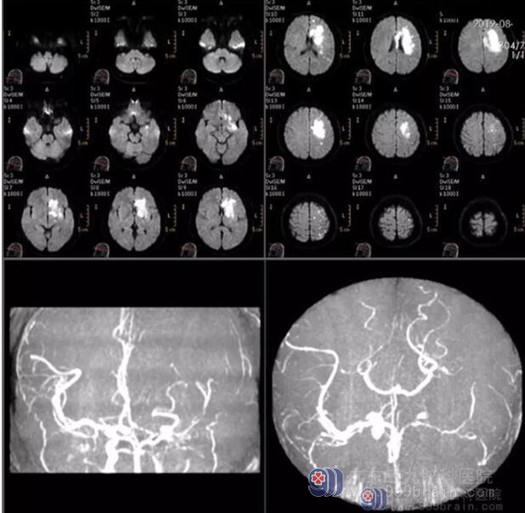

入院完善相关检查,DWI提示左侧额颞顶叶、基底节区-半卵圆中心及胼胝体大面积脑梗塞(偏亚急性期);脑MRA示左侧颈内动脉海绵窦及以上血管基本闭塞,左侧大脑中、大脑前动脉明显变细,分支减少,左侧大脑后动脉存在一定代偿。